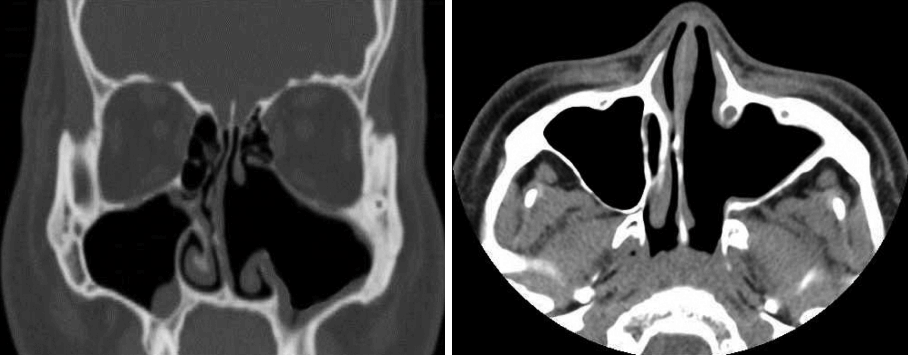

22세 남자가 내원 1년 전부터 심화되는 좌측 코막힘을 주소로 내원하였다. 환자는 1년 전 만성비염으로 개인병원에서 코블레이터를 이용한 하비갑개 성형술을 시행받았으며 수술 이후 좌측 비폐색이 점차 심해져 추가적인 검사 및 치료를 위해 본원을 방문하였다. 과거력상 비염 외 특이질환은 없었고 이전의 안면 및 부비동의 수술이나 외상의 과거력은 없었다. 또한 가족력상에서도 특이사항은 없었으며, 일반 혈액검사 및 일반 화학검사, 혈청검사 및 혈액응고검사상에서도 특이소견은 보이지 않았다. 비강 내시경 소견상 좌측 하비갑개 전방부에 코블레이터 삽입 위치로 보이는 반흔조직이 관찰되었으며 하비갑개 후방부의 비후소견이 관찰되었고 비후조직으로 인해 중비도 및 후비강의 확인은 불가능하였다(Fig. 1). 우측 비강은 심한 비중격의 우측편위 소견을 보였고 종물 등의 특이소견은 보이지 않았으며 비인두에도 특이소견은 관찰되지 않았다. 조영제를 사용한 부비동 전산화단층촬영에서 좌측 상악동을 가득 채운 균일하지 않게 조영 증강된 종괴가 관찰되었으며 종괴는 상악동 내측벽을 밀어내며 팽창하는 양상을 보였다(Fig. 2). 좌측 전사골동부 일부에 부비동염 소견 외 나머지 부비동에 이상소견은 보이지 않았으며 안와저골부의 침범소견도 관찰되지 않았으나 팽창성 종괴에 의해 비중격이 반대편으로 밀리는 소견이 관찰되었다. 혈관종이나 반전형 유두종 및 신경섬유종, 기질화 혈종 등이 의심되어 진단 및 치료를 위해 전신마취 하에 내시경적 접근을 통한 종괴의 절제술을 계획하였다. 수술 시 비강을 통해 내시경 접근법으로 종괴의 변연을 확인하였고 좌측 상악동의 내측 후방 기원의 종괴임을 확인한 뒤 회전절삭기 및 소작기를 사용하여 종괴를 조각 내어 제거하였다. 혈종 발생부위는 상악동 내측 후방부였으며 박리과정에서 접형구개동맥의 분지로 추정되는 동맥의 출혈이 발생하여 흡입기가 연결된 단극성 소작기를 통해 출혈을 조절하였다. 배출된 종괴의 내부는 혈관이 잘 발달되어 있었고 섬유화가 진행되어 단단한 질감이었으며 종괴의 외측부에는 점액성 액체가 포함된 점액낭종이 일부 관찰되었다(Fig. 3). 술 후 병리조직학적 소견에서 종괴는 내부에 풍부한 신생혈관들과 섬유화가 관찰되어 기질화 혈종으로 진단되었다(Fig. 4). 수술 이후 환자의 코막힘 증상은 사라졌으며 6개월간 추적관찰을 한 결과 종괴의 재발소견은 보이지 않았고 부비동 전산화단층촬영상 비중격의 우측 편위도 다소 정상으로 돌아온 것이 확인되었다(Fig. 5).